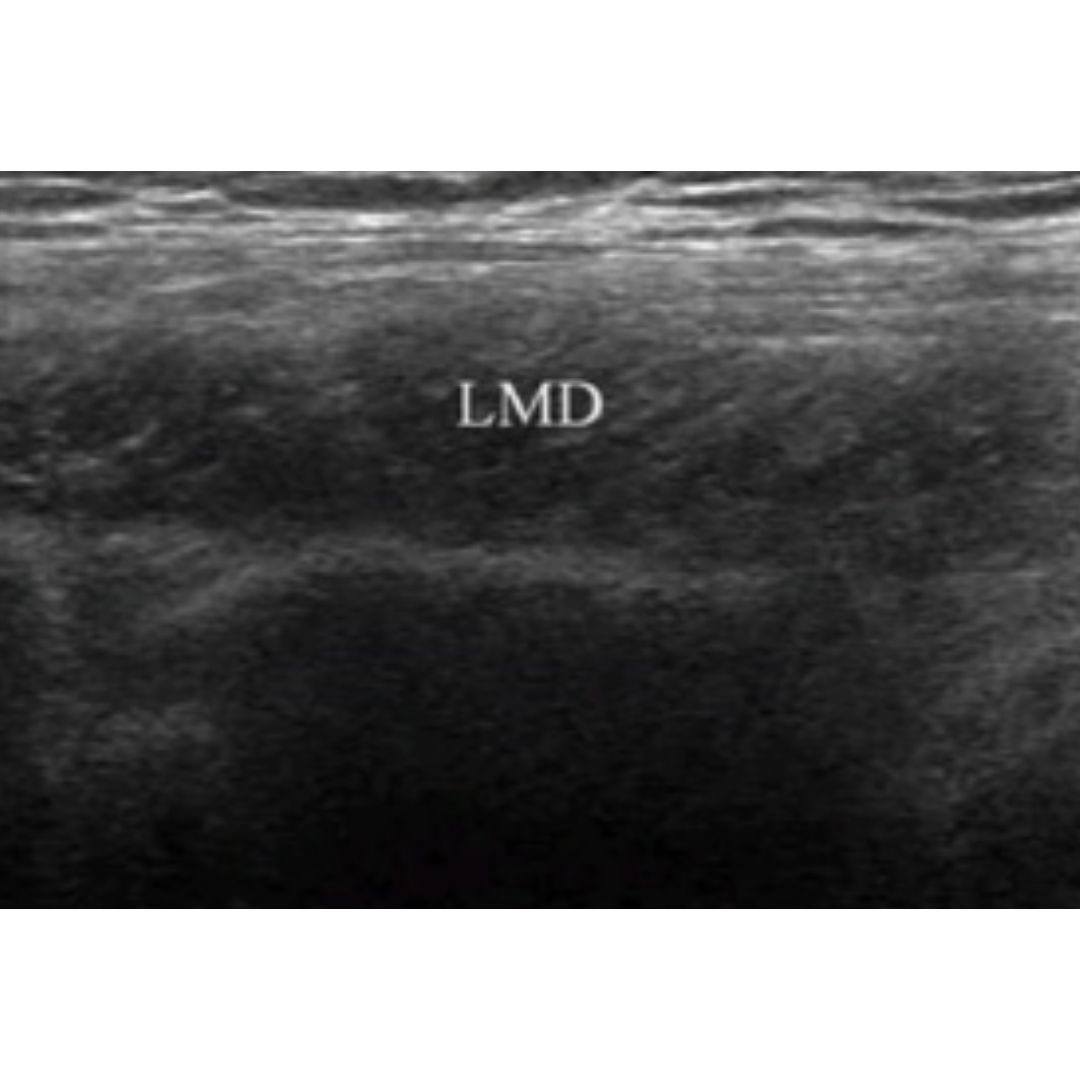

Imagen 4: Corte longitudinal. LMD: músculo dorsal ancho